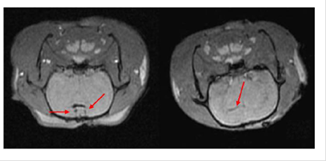

SPIOs have been used as MRI contrast agents since 1990.72 Currently, they are clinically used for liver imaging,70, 72 lymph nodes imaging,70 and blood pool agent.70 Although not initially developed for stem cell labeling and tracking,70-78 they have been successfully adapted for tracking stem cells post implantation.78, 79 Among them, Ferumoxides and ferucarbotran are most frequently usedprobably because of the regulation by U.S. Food and Drug Administration (FDA) and European Medicines Agency (EMA). Since the approval by FDA in 2009 for iron-deficiency anemia, ferumoxytolalso attracts lots of attention as contrast agents for stem cells tracking.77 All three NPs have been successfully used to label rat or human mesenchymal stem cells (MSCs),80, 82 embryonic stem cells (ESCs),84, 86 olfactoryensheathing cells (OECs),81 and neural stem cells (NSCs) 83, 84. For example, NSCs harvested from brain tissue of neonatal Sprague Dawley rats were labeled with ferucarbotran (Resovist®) and transplanted into rats of middle cerebral artery occlusion model by injection of cell suspension into ventricles.80-87 Following injection, MRI revealed that NSCs migrated from right lateral ventricle to the cerebral ischemic regions 2 weeks post-transplantation (Figure 6).87

Fig 6

MRI of transplanted Resovist®-labeled NSCs in the rat brain. At 1 hour following transplantation of Resovist®-labeled NSCs (T2 fast-gradient echo sequence), arrows reveal two symmetrical and horizontal pinholes (left). At 2 weeks post-transplantation, the arrow reveals the migration of Resovist®-labeled NSCs from the right lateral ventricle to the ischemic area (right). (Reprinted and adapted with permission from NRR, reference 87).